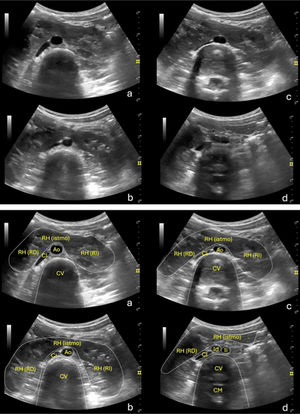

Cortes ecográficos donde se visualiza el RH (arriba) con identificación de las diferentes estructuras (abajo). a)Corte transversal del abdomen a nivel de la línea media de epigastrio inferior, donde se visualiza el istmo (RH [istmo]) del riñón en herradura (RH), que une a ambos riñones por sus polos inferiores (derecho: RH-RD; izquierdo: RH-RI). Inmediatamente debajo del mismo se visualizan dos estructuras anecogénicas, una de morfología circular, que corresponde a la aorta descendente (Ao), y otra fusiforme, de disposición oblicua y a la izquierda de la anterior, que corresponde a la vena cava inferior (CI). b)Corte similar al anterior, inmediatamente debajo del mismo, donde se expone un mayor espesor de ambos riñones. c)Corte similar a nivel de mesogastrio, donde la Ao comienza a dividirse en las dos arterias iliacas. d)Corte inmediatamente debajo del anterior, donde se visualiza la porción inferior del istmo y polo inferior del RD (más caudal que el contralateral) y las dos arterias iliacas (Id: derecha; Ii: izquierda) tras la bifurcación de la Ao.

CM: canal medular; CV: cuerpo vertebral.

a)Corte transversal del abdomen a nivel de la línea media de epigastrio inferior, con Doppler color, donde se visualiza el RH, la Ao (en rojo) y, a la izquierda, la CI (en azul y mezcla de azul y rojo). b)Imagen previa con delimitación del RH. c)Corte oblicuo a nivel de hipocondrio izquierdo donde se objetiva el riñón izquierdo y su vascularización, mediante Doppler color. d)Imagen previa con delimitación del RI.